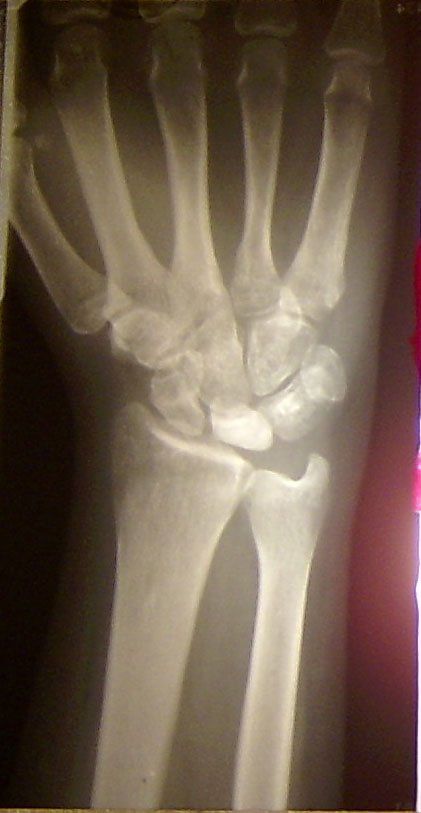

Das MRT brachte den Befund "Lunatummalazie" und die überweisung zum Handchirurgen Dr. Jung. Die Lunatummalazie war bereits im II. Stadium. Somit wurde eine Eigenknochenmarkstransplantation durchgeführt. Das hieß ca. eine Woche Krankenhausaufenthalt. Ich kann beruhigen, die Schmerzen sind nicht groß und auch die Einschränkungen durch die OP halten sich in Grenzen. Nach der OP musste ca. 6 Wochen eine Gipsschiene getragen werden. Ich gewöhnte mich schnell daran, damit umzugehen.

Ich hatte jedoch nach einem halben Jahr erneut Beschwerden. Meine Lehre konnte ich auf Grund der Lunatummalazie nicht weiter ausüben. Und nach dieser Zeit begannen die Schmerzen im Handgelenk erneut mit jeder Bewegung. Wie sich bei einer weiteren Röntgenaufnahme feststellen ließ, hatte das Mondbein sich nicht - wie eigentlich geplant war - regeneriert und aufgebaut, sondern weiter zersetzt. Somit musste eine erneute Operation durchgeführt werden.